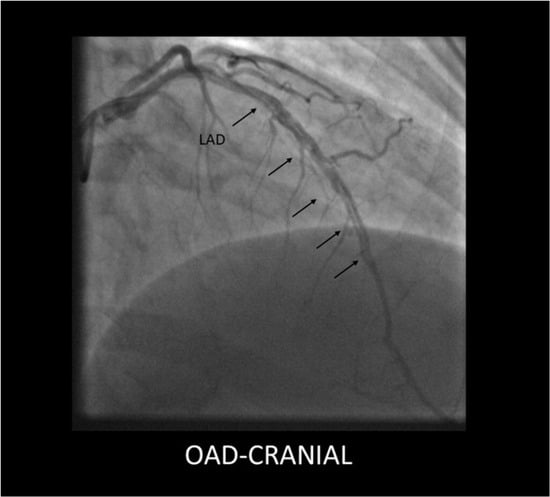

- SCAD Type 1 (classic aspect)—double lumen and longitudinal filling defect, indicating the presence of a false lumen (wall contrast staining) and visible intimal flap. This aspect is pathognomonic for dissection and easily recognizable; however, it is present in fewer than a third of diagnosed SCAD cases. The presence of contrast inside the coronary wall (“dye hang-up” sign) suggests an already formed dissection, often with a late presentation and fewer chances of further progression [,] (Figure 1).

Type 1 SCAD lesion originating in the mid segment of the LAD, showing a long dissection flap (black arrows).